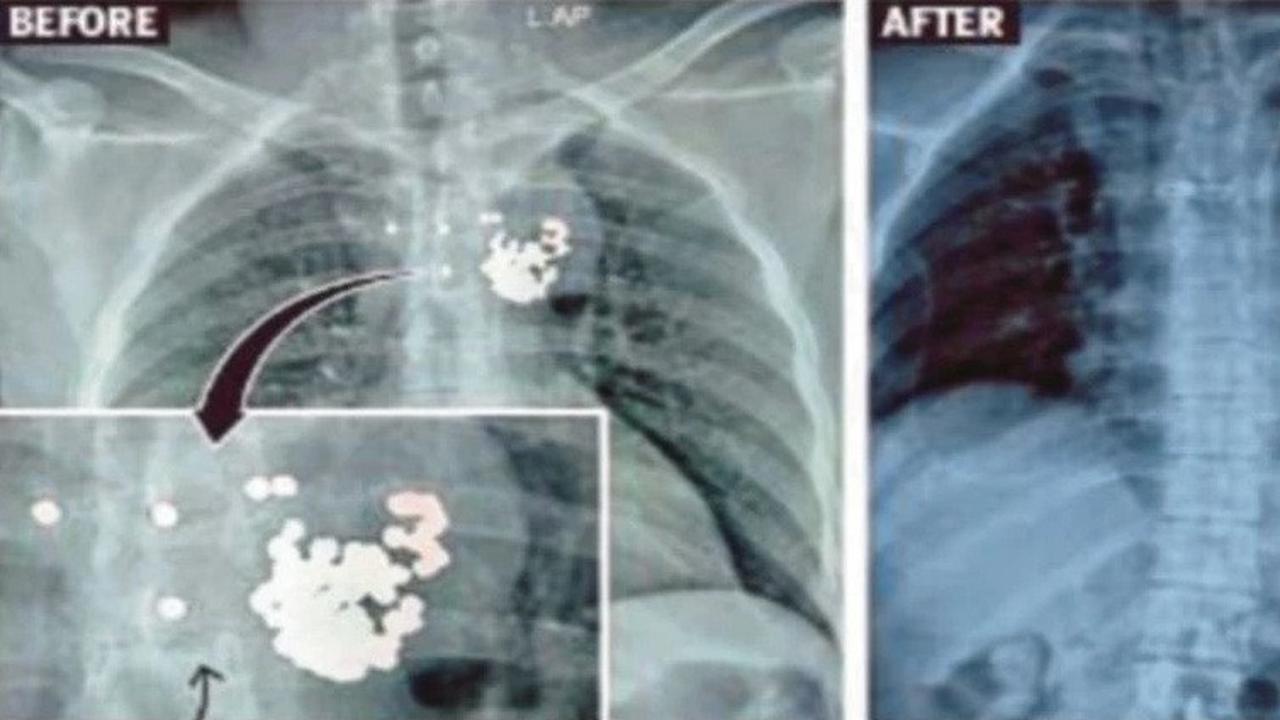

Liputan6.com, Jakarta Seorang pria yang hidup selama empat tahun dengan 97 peluru di dadanya, berhasil menjalani operasi untuk mengangkat benda tersebut. Ia tertembak dari jarak dekat saat tidur dengan saudaranya, untungnya peluru tersebut tidak ada yang menembus jantung atau paru-paru.

Butuh waktu seharian untuk mengangkat semua peluru tersebut dengan hati-hati. Salah sedikit saja, nyawa Aarif melayang. Untungnya, semua berjalan lancar dan pria itu dalam keadaan stabil setelah operasi.